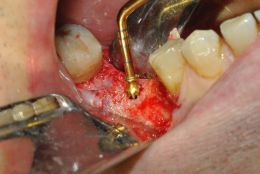

Preparazione del sito implantare con ultrasuoni, si previene l'insorgenza di deiscenze e fenestrazioni tipiche del twist drill da 3.5mm in creste con moderato riassorbimento orizzontale

Piezosurgery: preparazione del sito implantare in 46

PREPARAZIONE DIFFERENZIALE DELLA CORTICALE LINGUALE CON INSERTO DIAMANTATO OT4

PREVENZIONE DELLA DEISCENZA VESTIBOLARE